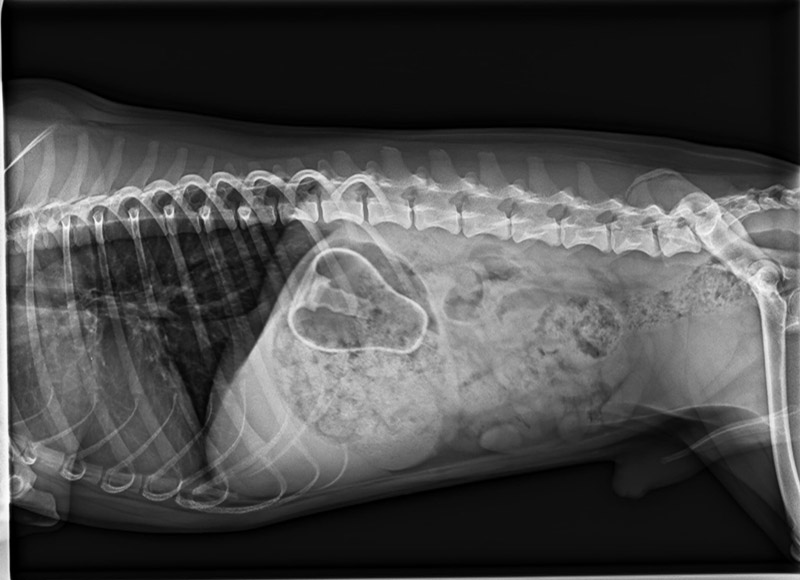

Pflegehund Luis hatte richtig Pech. Leider hatte er seine Quitschiebirne zum Fressen gerne. Diese hing im Magen fest, sodass eine Notfalloperation durchgeführt werden musste.

Zum Glück ist alles gutgegangen. Dem kleinen quirligen Mann geht es wieder gut.

Aber es gab natürlich auch eine Rechnung über 1000 Euro, die ein Loch in unsere Kasse gerissen hat. Also bitte seid vorsichtig, von diesen weichen Spielzeugen raten wir dringend ab. Eine gute Alternative sind die Vollgummispielzeuge von Kong, sie sind nahezu unverwüstlich. Spielzeug sollte natürlich auch nur unter Aufsicht benutzt werden, aber das entspricht meist nicht dem praktischen Alltag. Also lieber hochwertiges Spielzeug kaufen und möglichst die Augen offen haben.